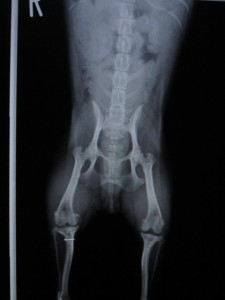

術前のレントゲンです。

両側膝蓋骨脱臼も見られます。